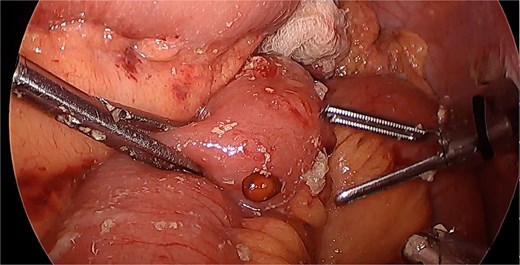

The laparoscopy revealed a preserved gastric pouch but distended small bowel loops. The anastomoses were intact. During the disassembly of the jejunojejunostomy, undigested solid food, including seeds, was found to be causing an intestinal obstruction (Fig. 2). This finding was consistent with a phytobezoar, which had led to the obstruction. The obstructing material was removed, and the anastomoses were reconstructed. Additionally, mesenteric gaps were closed, and a left subphrenic drain was placed to manage postoperative effusions and prevent further complications.